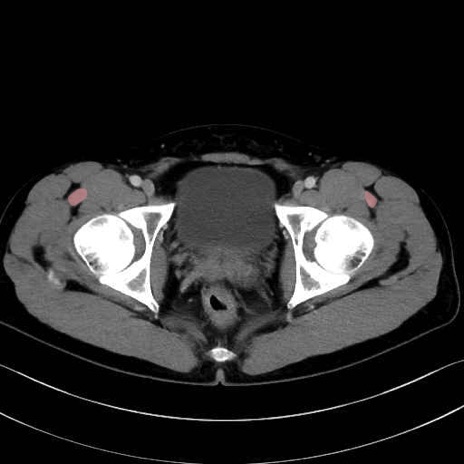

大腿直筋 (Rectus femoris)